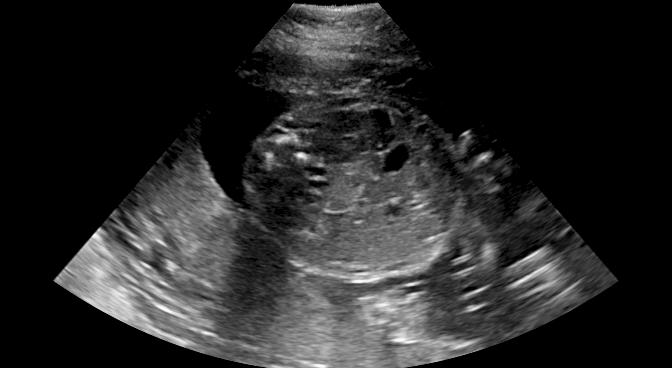

Routine US screening is usually performed using a single 2D probe. However, the position of the probe and resulting tomographic view through the anatomy has great impact on diagnosis. Zimmer et al. [39] proposed a multi-view image reconstruction method, which compounds different images of the same anatomical structure acquired from different view directions. They use a Gaussian weighting strategy to blend intensity information from different views. Here, we combine predicted shadow confidence maps from these multi-view images as additional image fusion weights to investigate if these confidence maps can further improve image quality.

The proposed method generally outperforms the baseline and the proposedAG method, thus we only integrate the shadow confidence maps generated by the proposed method () into the weighting strategy in [39]. In detail, the probability value of each pixel in a shadow confidence map is multiplied to the original weight of the same pixel computed in [39]. The generated new weights are normalized as described in [39] and then are used for image fusion. The data set in this experiment is same as used for [39].

Fig. 9 qualitatively shows that shadow confidence maps are able to improve the performance of US image fusion algorithms with different weighting strategies. Fig. 9 also shows the difference between adding two different types of confidence maps. These two types of confidence maps are generated by the confidence estimation network which are separately trained by either MSE or Sigmoid loss. Fig. 9 (a) to (d) illustrate image fusion results for the same case using different combinations of weighting strategies and loss functions. The difference maps indicate that shadow confidence maps are capable of improving image fusion performance. Fig. 9 (e) to (h) show image fusion results on four different cases. We randomly select two positively affected cases (Fig. 9 (e) and (f)) to show visual improvement. We additionally show two randomly selected examples (Fig. 9 (g) and (h)) that don’t show perceptually significant improvements after adding shadow confidence maps. Quantitative evaluation for image fusion is not possible because of lacking a ground truth for US compounding tasks.